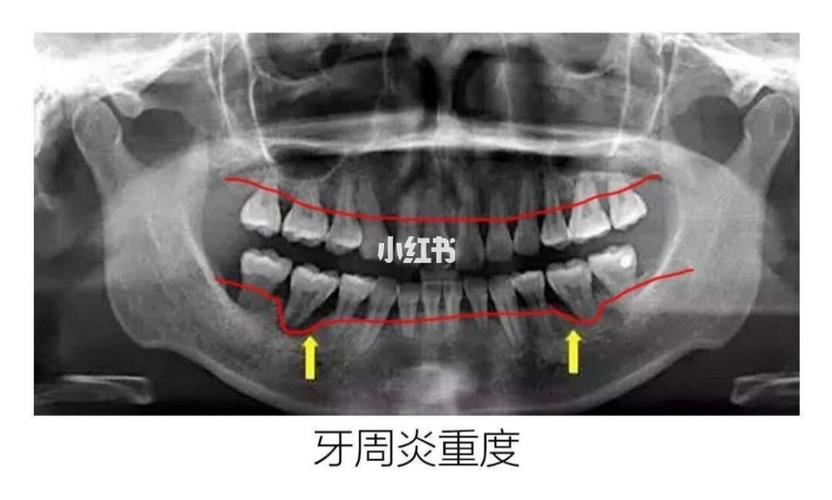

【教你如何通过x光片了解自己的牙周情况】_牙周炎_牙齿保护_口腔